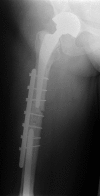

Custom-made endoprostheses can be linked to existing well-fixed implants in the treatment of complex periprosthetic femoral fractures. By adopting this salvage approach, secure implants can be retained in favour of patients undergoing more tissue disruptive procedures such as total femoral replacements. In this piece, we present a unique case illustrating a salvage strategy for treating a failed cement-linked salvage endoprosthesis, a complex scenario which to our knowledge has never before been reported.